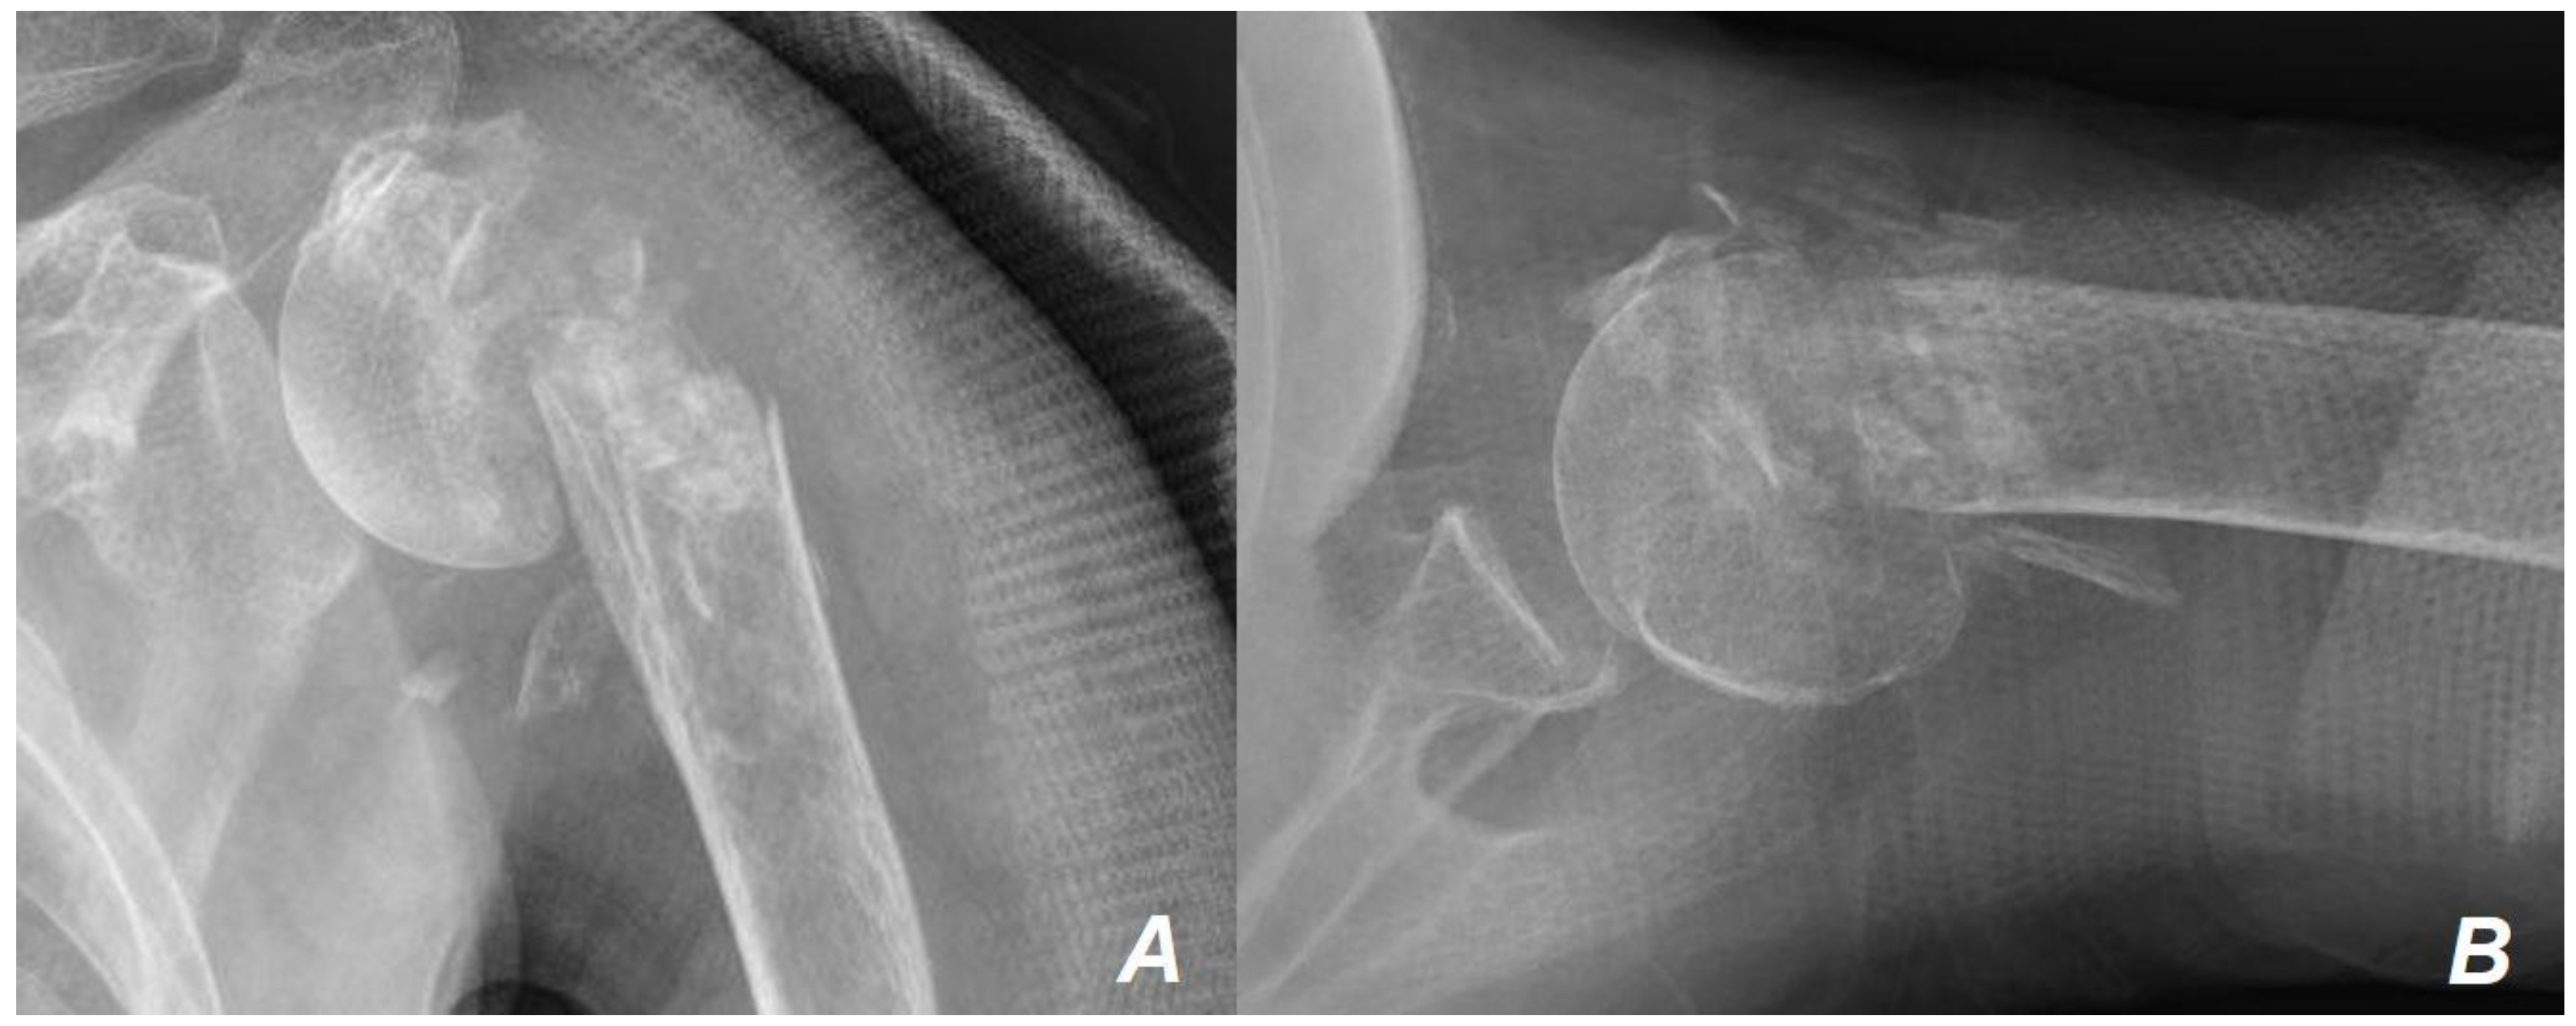

2. Case Presentation

| Age at surgery | 88 |

| Sex | Female |

| Diagnoses | Severe osteoporosis (T-score −4.6 at the femoral neck) |

| Mild hypertension on medication | |

| Neer 4-part proximal humerus fracture on the left shoulder | |

| Physical Examination | Decreased painful range of motion in the left shoulder |

| Functional demand | Independent light household activities |

| Osteoporosis medication | None |

| Past medical history | None |